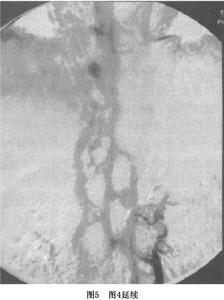

4.血管造影血管造影是明確BCS病變部位的最重要方法。一般可通過以下3種方法了解肝靜脈及下腔靜脈形態和血流動力學變化(圖3,4,5)。

(2)經肝靜脈插管:肝靜脈阻塞時最好經肝作肝靜脈插管測壓及造影。此時肝靜脈壓顯著增加,注入造影劑可顯示梗死部位程度、形態可見肝靜脈間各種側支循環將血液引流入右心房或反流入門靜脈肝內血管呈蜘蛛網狀。此時若同時行下腔靜脈造影則可更清楚地了解肝靜脈受累情況。即使經肝靜脈插管不能成功行肝實質造影也可明確診斷。但是,有嚴重出血傾向和大量腹水的病人,禁忌行肝實質穿刺造影。